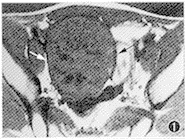

手术所见:肿物位于内环口上方腹膜外,约10cm×9cm×8cm大小,圆形,光滑,包膜完整,质硬,与周围无粘连,周围淋巴结不大。病理:镜下见瘤组织成分单一,由圆形或多角形瘤细胞构成,胞浆透明,核大,核仁位于中央,核膜清晰,可见核分裂(图 4)。病理诊断:睾丸精原细胞瘤(右侧)。

图4 标本病理切片:瘤细胞胞浆透亮,有明显细胞界,核大而圆,位于中央,核仁易见,可见核分裂,瘤细胞排列呈巢状(HE×400)